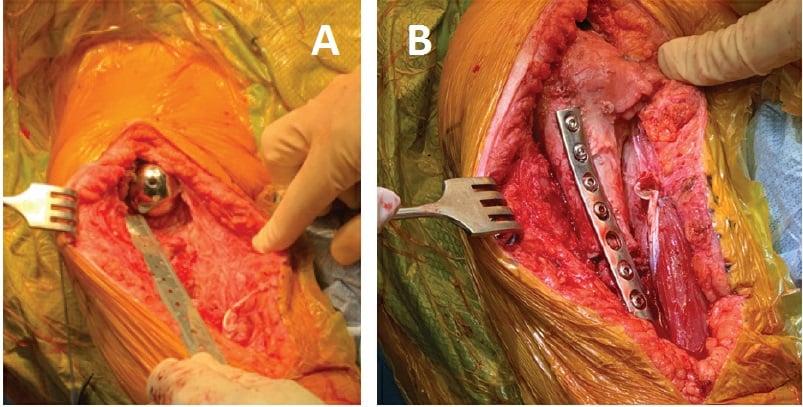

The patient underwent revision rTSA of the humeral component only, using an allograft-prosthetic composite (APC), rotator cuff repair, and biceps tenodesis. The proximal humerus was exposed via an extended deltopectoral approach, and biopsies and frozen sections were obtained. With no evidence of infection, a single-stage revision proceeded.

The humeral prosthesis was grossly loose proximally but fixed distally, and the surrounding proximal humeral bone was of poor quality and largely nonviable. Metal cerclage wires were removed, as were the prosthesis and 9 cm of proximal humeral bone, with a transverse cut made 1.5 cm distally to the area of bone loss. The stem was extracted with a combination of the Midas Rex drill and narrow flexible osteotomes.

The allograft was then fashioned for use; 9 cm of the proximal humerus was matched to the defect for placement of a revision stem. Of note, the allograft was prepared on the back table to accept the inlay humeral prosthesis and then transferred to the patient to allow for the stem to bypass the allograft–humeral diaphysis interface. The APC was trialed, and satisfied with our length and proximal articulation we fixed an anterior plate both proximally into the allograft and distally into the remaining humeral shaft (Fig. 3).

Figure 3: Intraoperative photographs show (a) the humeral defect after component explantation and (b) the final humeral prosthesis with allograft and plate fixation.